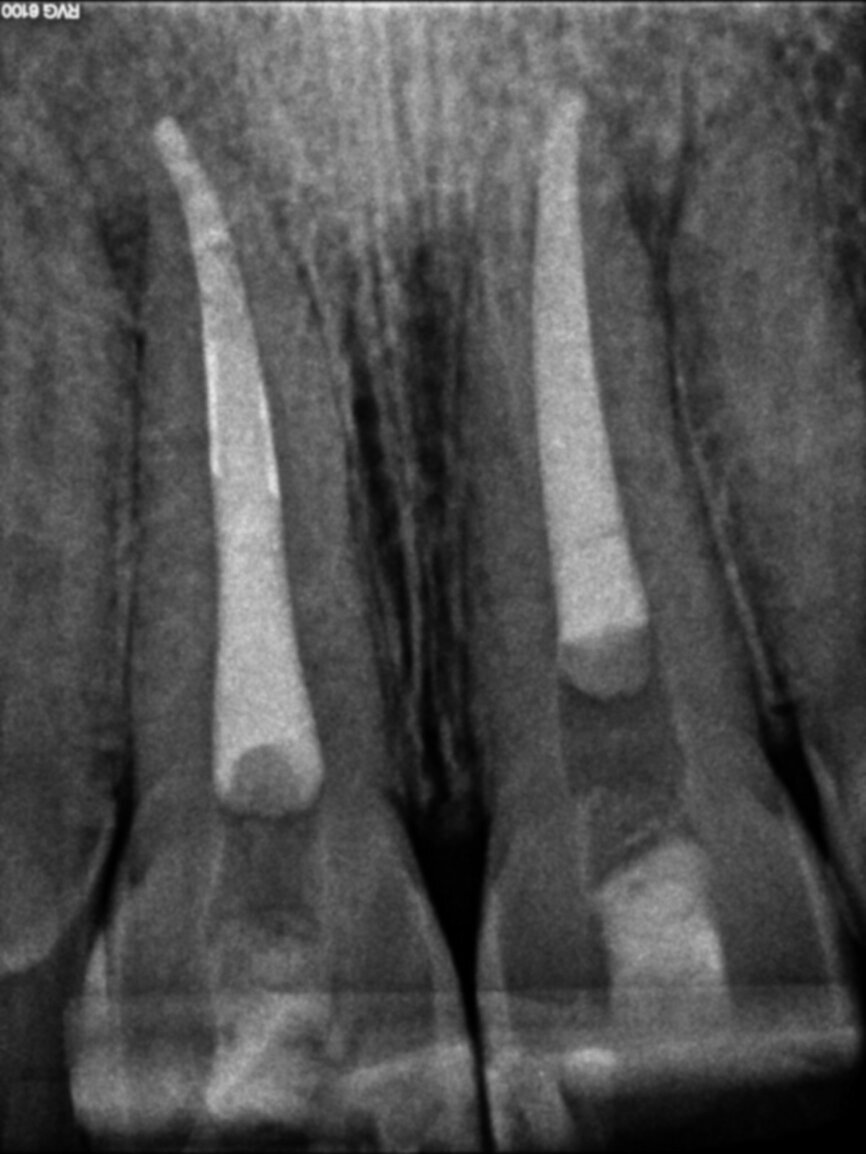

Post-operative radiograph (Image: Dr Vittorio Franco, UK and Italy)

The 22-year-old male patient had a history of trauma to his maxillary incisors and arrived at my practice with symptoms related to tooth #21. The tooth, opened in an emergency by the patient’s mother, was tender when prodded, with a moderate level of sensitivity on the respective buccal gingiva. Sensitivity tests were negative for the other central incisor (tooth #12 was positive), and a periapical radiograph showed radiolucency in the periapical areas of both of the central incisors. The apices of these teeth were quite wide and the length of teeth appeared to exceed 25 mm.

I suctioned the sodium hypochlorite, checked the working length with a paper point and then obturated the canal with a of 3 mm in thickness plug of bioactive cement. I then took a radiograph before obturating the rest of the canal with warm gutta-percha. I used a compomer as a temporary filling material.

The symptoms resolved, so I conducted the second treatment only after some months, when the tooth #11 became tender. Tooth #21 had healed. I performed the same procedure and obtained the same outcome (the four-month follow-up radiograph showed healing).